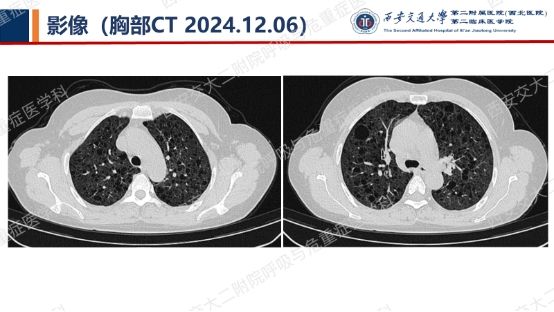

阅影探案,析病寻踪 // 第一期(上)

影像方寸藏玄机,同影异病辨真章。让我们一起抽丝剥茧,揭秘医学真相,解锁临床那些有意思的病例谜题吧!

结合以上患者病史及胸部CT,第一诊断分别考虑???欲知答案,且看后期!!!